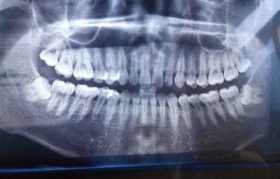

拔智齿的价格因多种因素而异,包括智齿的位置、拔除难度、医院等级、地区差异等。本文将全面解析拔智齿的费...